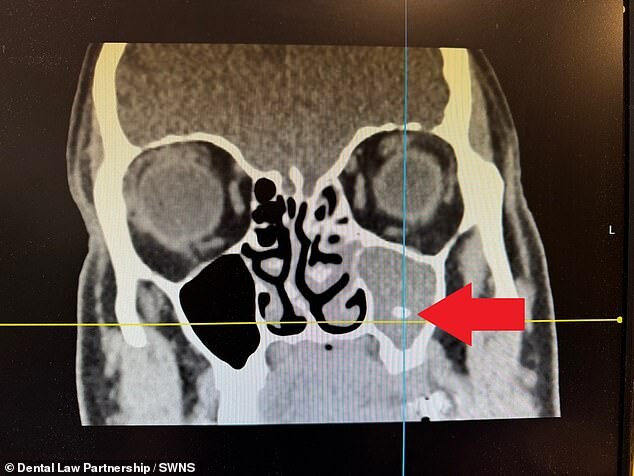

В конце концов, после двух лет страданий, сканирование показало, что часть одного из удаленных зубов находится в его пазухах. И удалив ее - мужчина решил обратиться в суд. "Я знал, что все идет не так, как надо, поскольку стоматолог с большим трудом вытаскивал зуб", - сказал Шир в интервью SWNS. "Все это было очень страшно. Мне очень повезло, что в конце концов причина боли была обнаружена, я и представить себе нее мог, что такое может случится из-за простого удаления", - добавил он.

Только в июне 2022 года Шира направили в больницу, где компьютерная томография показала, что у него левосторонний синусит, который был вызван тем, что в пазуху попал кусочек зуба. "Из-за синусита я чувствовал себя так, будто постоянно простужен", - сказал он. "Из-за заложенного носа было трудно дышать, а во рту всегда был ужасный привкус. Я часто не мог заснуть и иногда не мог пойти на работу, потому что голова сильно болела. Все это было очень неприятно, и даже пугало. Мне очень повезло, что в конце концов болезнь была обнаружена… я никогда не думал, что все мои страдания исходят от зуба, который был неправильно удален". После пережитого Шир вернулся к своему стоматологу в ноябре того же года, чтобы рассказать ему о том, что произошло в результате его лечения. Но перед ним даже не извинились за неудачное удаление зуба.